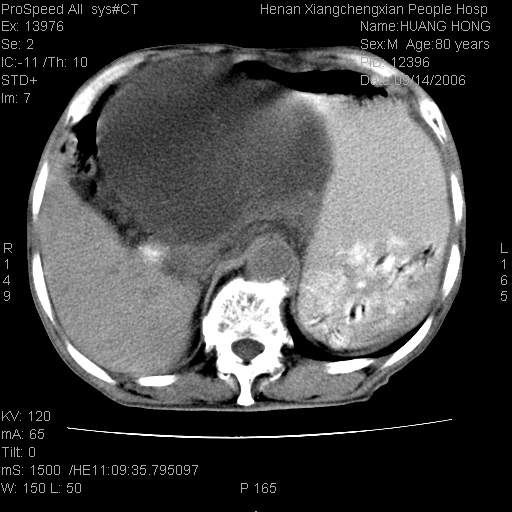

患者, 男, 80岁, 发现上腹部包块1年余,无其它不适.2006-9-14ct片是喝水后扫描2006-9-15ct片没喝水扫描![]() ![]() ![]() ![]() ![]() ![]() ![]() ![]() ![]() ![]() ![]() ![]() ![]() ![]() ![]() ![]() 以上是喝水片 以下是空腹片 ![]() ![]() ![]() ![]() ![]() ![]() ![]() ![]() ![]() ![]() ![]() ![]() ct:胰腺前方、肝脏与胃之间可见巨大类圆形囊性低密度影,大小约152mmx145mmx118mm,上缘平t11椎体上缘,下缘平l3椎体下缘,密度均匀,ct值15hu,其内呈多房分隔,囊壁薄且光滑,边界清晰,周围组织及器官明显受压。肝脏实质内未见异常密度影,胆囊未见异常,胰腺密度未见异常,脾脏大小、形态及密度未见异常,腹膜后间隙未见肿大淋巴结影。 印象:胰腺前方、肝脏与胃之间巨大类圆形囊性低密度影.性质待定。多考虑:.肠系膜巨大囊肿。 守望可可西里发言:支持楼主,考虑肠系膜囊肿,多为小肠系膜。 ysxyy发言:我总觉得这个病人虽然很像肠系膜囊肿,但还是应该强化一下; 下面这几幅图里肿块和主动脉的关系不太清,不知能否除外血管性来源? ![]() ![]() ![]() 病理结果:横结肠系膜间叶瘤.部分区域间质细胞增生活跃. 病理图片 ![]() 良性间叶瘤:是指由两种或两种以上的间叶组织所构成的混合性肿瘤.肿瘤仅发生在腹膜后和肠系膜,.前者较后者多发.良性间叶瘤常发生在肾或四肢,腹膜后较少见,各年龄均可发病.女多与男,预后较好,但术后易复法. 恶性间叶瘤:由两种以上恶性间叶组织成分组成. 光镜:肿瘤由脂肪/血管/平滑肌构成. 原贴地址: http://www.radinet.com.cn/forum_view.asp?forum_id=4&view_id=16217 ok |